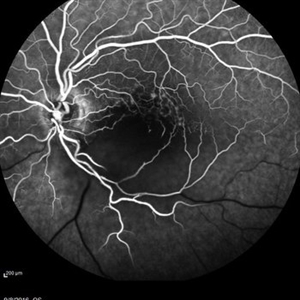

Central Retinal Vein Occlusion with Severe Ischemia

May 22 2016 by Olivia Rainey

Composite fluorescein angiogram of the left eye of a male with a Central Retinal Vein Occlusion with severe ischemia.

Photographer: Olivia Rainey

Imaging device: Heidelberg Spectralis

Condition/keywords: central retinal vein occlusion (CRVO), composite, fluorescein leakage, ischemic CRVO